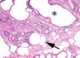

Brunner gland hyperplasia

Brunner's glands (or duodenal glands) are compound tubular submucosal glands found in that portion of the duodenum which is above the hepatopancreatic sphincter (i.e sphincter of Oddi). The main function of these glands is to produce a mucus-rich alkaline secretion i.e. [Source: Wikipedia ]